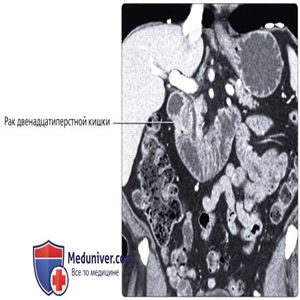

КТ с контрастированием, аксиальный срез: определяется локальное утолщение стенки горизонтальной части двенадцатиперстной кишки в виде объемного образования в сочетании с аневризматическим расширением и изъязвлением, являющееся проявлением рака двенадцатиперстной кишки, подтвержденной в ходе хирургического удаления.

КТ с контрастированием, корональный срез: определяется кольцевидное сужающее просвет органа объемное образование преампулярного отдела двенадцатиперстной кишки, являющееся проявлением рака двенадцатиперстной кишки. По сравнению с другими потенциальными злокачественными образованиями этой области ампулы (например, рак поджелудочной железы, холангиокарцинома дистального отдела ОЖП или рак ампулярного отдела) рак двенадцатиперстной кишки характеризуется более благоприятным прогнозом.

КТ с контрастированием, аксиальный срез: выраженное расширение луковицы двенадцатиперстной кишки с резким сужением и утолщением на уровне нисходящего отдела двенадцатиперстной кишки, что сочетается с раком двенадцатиперстной кишки и последующей обструкцией луковицы двенадцатиперстной кишки.